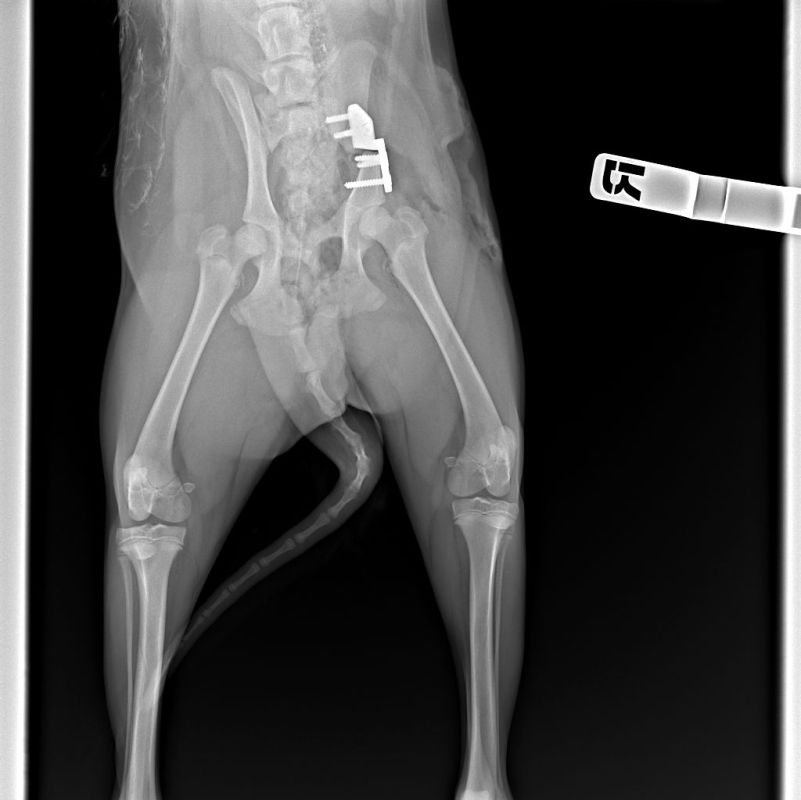

Использование малотравматичной эндоскопической хирургии значительно уменьшает объем оперативного вмешательства, снижает послеоперационную боль, и животное начинает наступать на лапу чаще уже в первые 2-3 дня после операции.

Оборудование для диагностики высокой точности

Какие патологии мы лечим